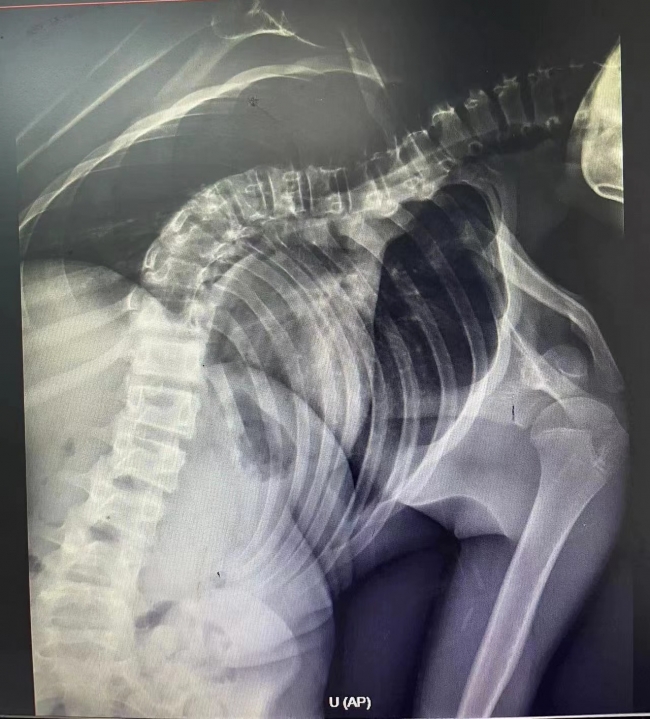

入院后,脊柱外科团队积极完善相关检查,杰杰因为脊柱侧弯达75度,被诊断为“特发性脊柱侧弯畸形”。“我们发现,他的脊柱侧弯由去年的68度,已经进展到现在的75度,为侧弯进展期,并且侧弯角度大于50度,具有有明确的手术指征。”李永斌说。

经过周密的术前讨论,脊柱外科团队成功为杰杰实施了特发性脊柱侧弯复位、截骨矫正、减压、内固定、植骨融合术。医务人员在杰杰的体内共置入14颗椎弓根钉,手术切口长达35厘米,手术历时5个半小时,术中每一个操作对于医生都是极大的考验。术后,患者生命体征平稳,脊髓神经检测无异常,杰杰终于挺直了胸膛,身体由入院时的153厘米增高至162厘米,一下子长高了9厘米。